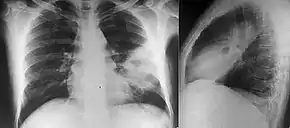

People with diabetes mellitus or regular exposure to the bacteria are at increased risk of developing melioidosis. The disease should be considered in those staying in endemic areas who develop fever, pneumonia, or abscesses in their liver, spleen, prostate, or parotid glands.[1] The clinical manifestation of the disease can range from simple skin changes to severe organ problems.[1] Skin changes can be nonspecific abscesses or ulcerations.[8] In northern Australia, 60% of the infected children presented with only skin lesions, while 20% presented with pneumonia.[3] The commonest organs affected are liver, spleen, lungs, prostate, and kidneys. Among the most common clinical signs are presence of bacteria in blood (in 40 to 60% of cases), pneumonia (50%), and septic shock (20%).[1] People with only pneumonia may have a prominent cough with sputum and shortness of breath. However, those with septic shock together with pneumonia may have minimal coughing.[2] Results of a chest X-ray can range from diffuse nodular infiltrates in those with septic shock to progressive solidification of the lungs in the upper lobes for those with pneumonia only. Excess fluid in the pleural cavity and gathering of pus within a cavity are more common for melioidosis affecting lower lobes of the lungs.[2] In 10% of cases, people develop secondary pneumonia caused by other bacteria after the primary infection.[3]

Various imaging modalities can also help with the diagnosis of melioidosis. In acute melioidosis with the spreading of the bacteria through the bloodstream, the chest X-ray shows multifocal nodular lesions. It may also show merging nodules or cavitations. For those with acute melioidosis without the spread to the bloodstream, chest X-ray shows upper-lobe consolidation or cavitations. In chronic melioidosis, the slow progression of upper-lobe consolidation of the lungs resembles tuberculosis. For abscesses located in other parts of the body apart from the lungs, especially in the liver and spleen, CT scan has higher sensitivity when compared with an ultrasound scan. In liver and splenic abscesses, an ultrasound scan shows "target-like" lesions, while CT scan shows "honeycomb sign" in liver abscesses. For melioidosis involving the brain, MRI has higher sensitivity than a CT scan in diagnosing the lesion. MRI shows ring-enhancing lesions for brain melioidosis.[9]